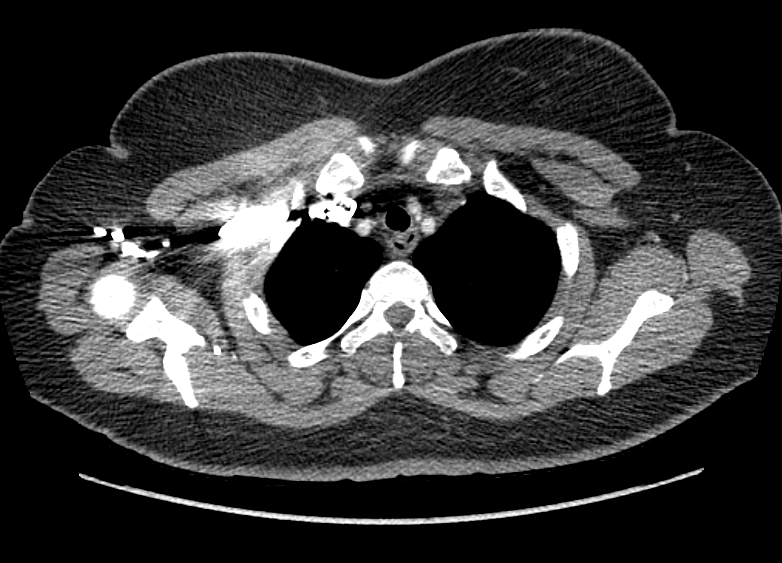

F/34

°Ç°­°ËÁø»ó ½ÃÇàÇÑ Chest PA »ó mediastinal widening ¼Ò°ßÀ¸·Î further evaluation À§ÇØ ³»¿øÇÔ.

Áõ»óÈ£¼Ò ¾øÀ¸¸ç ½Åü°ËÁø»ó ƯÀÌ¼Ò°ß ¾øÀ½.